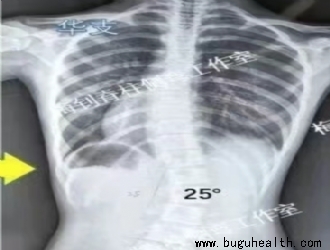

脊柱侧弯

脊柱侧弯支具更换指南:家长必看的3个关键信号

在青少年特发性脊柱侧弯的保守治疗中,定制化支具堪称"移动的矫正器"。作为矫形医学领域的核心工具,支具的精准适配直接关系到矫形成效。 .....